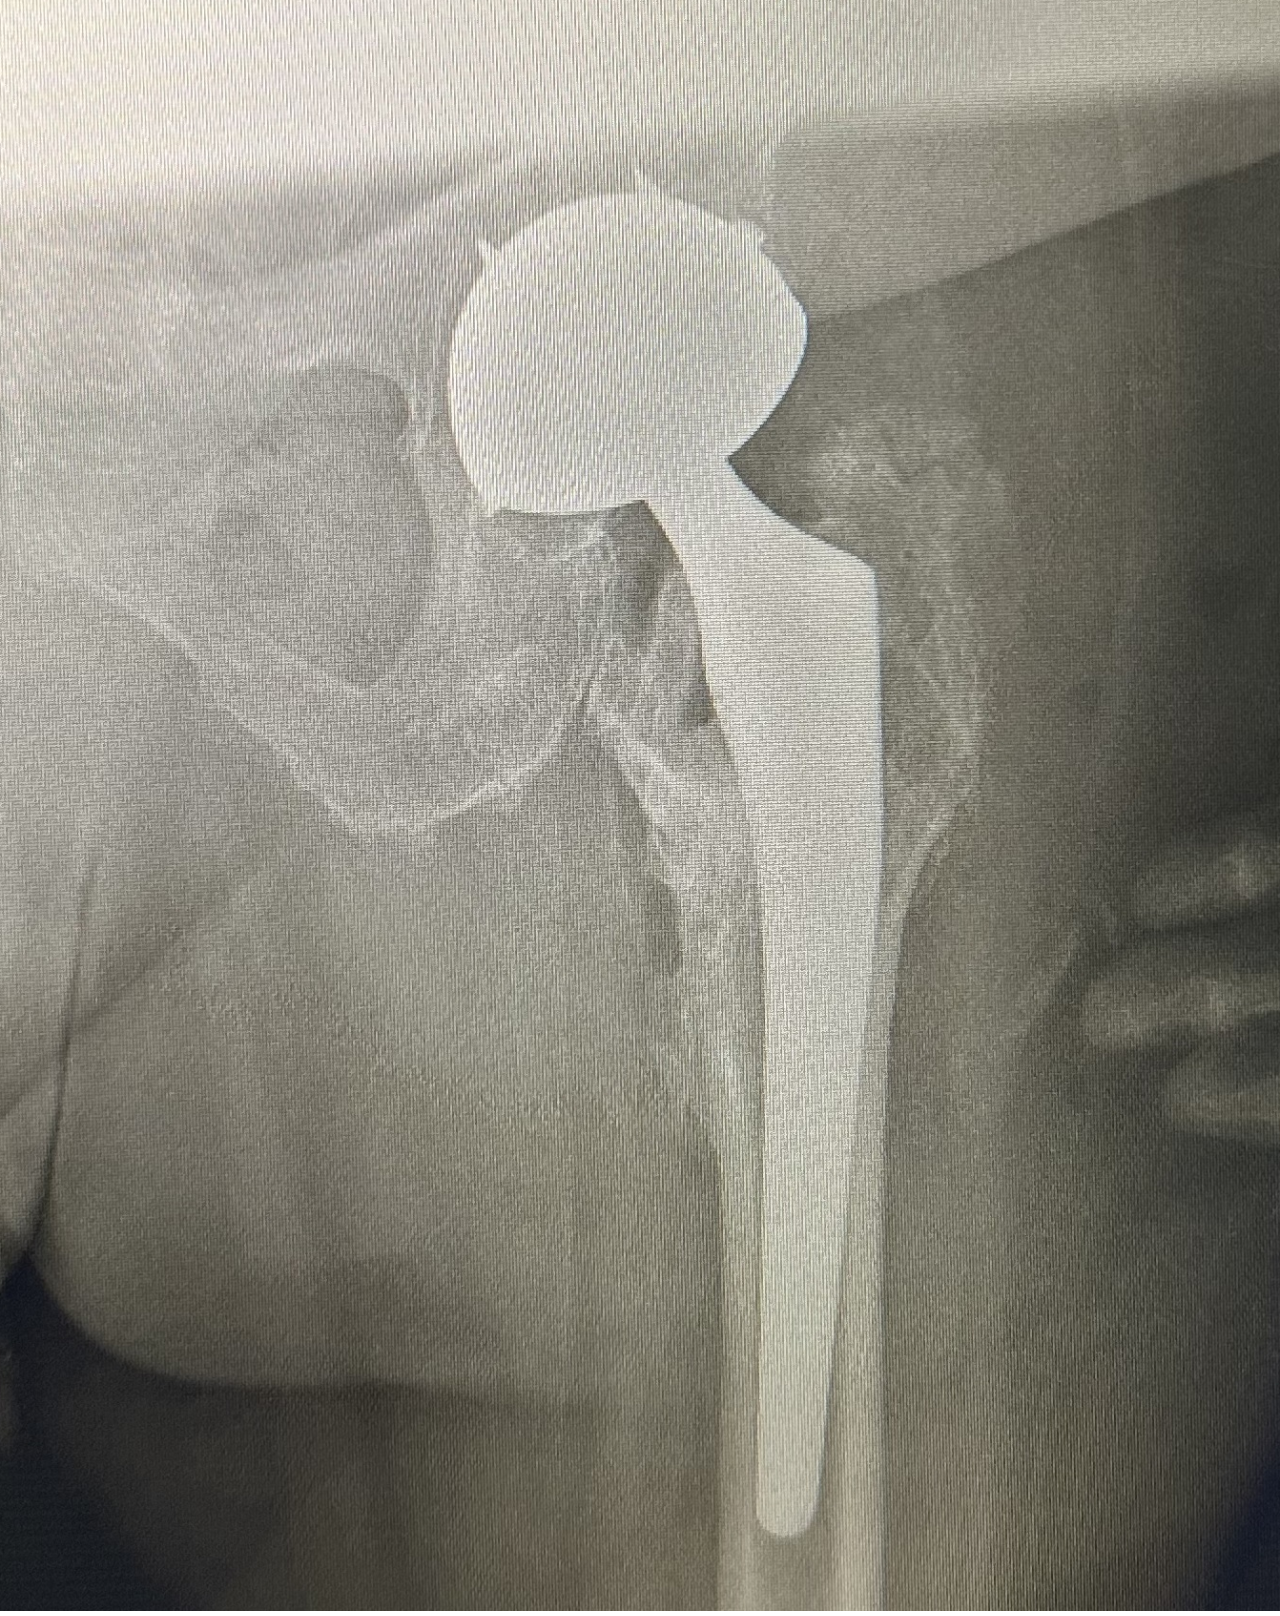

三、多功能牵引床辅助下直接前路(DAA)人工全髋关节置换术以及椭圆形髋臼假体、多翼型髋臼假体和双动型髋关节假体。牵引床的应用,更多地解放了医生的双手,在节省人力的同时,还为手术提供了稳定而持久的牵引力,极大地降低了髋关节置换的手术难度,使手术进行更加顺利。椭圆形髋臼、多翼型髋臼和双动型髋关节的问世,增加了髋关节的稳定性,为复杂的髋关节病例提供了有效的解决方案。